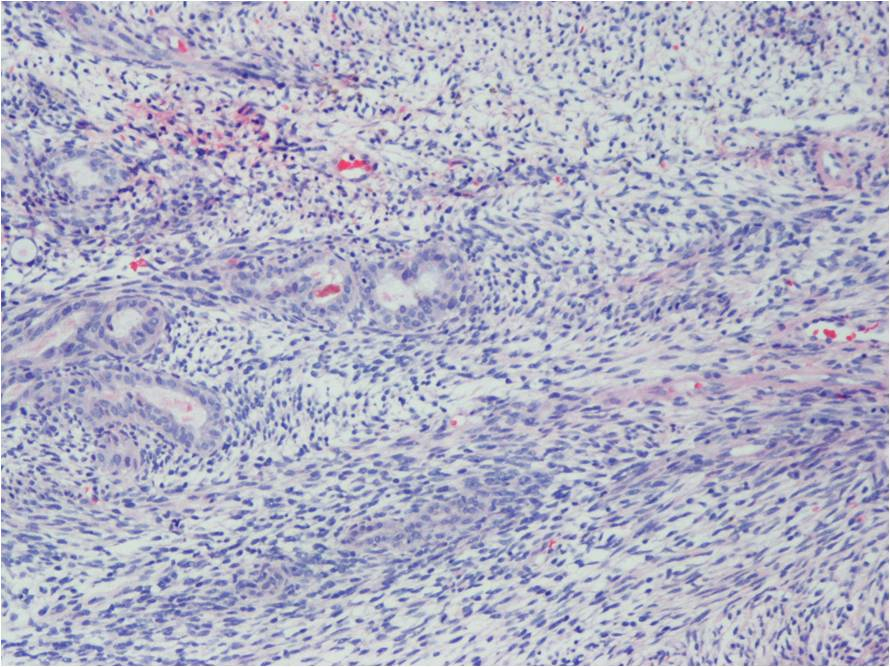

Microscopic Pathology

Synovial Sarcoma is composed of two different cell types

Spindle cell (small, uniform, and ovoid cells with pale nuclei and the cytoplasm is sparse)

Epitheloid cell (ovoid nuclei and abundant cytoplasm)

Biphasic form is composed of both epithelial-cell and spindle-cell components in equal proportions (Fig. 6-8)

Monophasic Fibrous type predominantly spindle cell.

Monophasic Epithelial type is difficult to differentiate from adenocarcinoma without cytogenetics and immunohistochemistry.

Poorly differentiated type demonstrates features of high grade small round cell tumor with dense cellularity, numerous mitotic figures, and areas of necrosis.

Inmunohistochemical profile: Vimentin (+), Cytokeratin (+), Epithelial Membrane Antigen EMA (+)